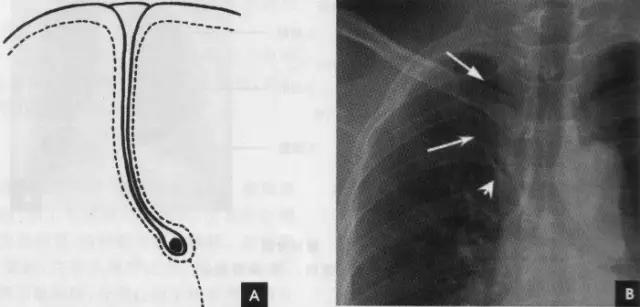

5、左肺下叶左肺下叶相当于右肺下叶所占据的肺野。除上述肺的分叶外,还可有先天变异而出现额外肺叶,称为肺副叶。副叶由肺叶间裂伸入肺叶内所形成。常见有下列4个: (1)奇叶系因奇静脉位置异常所致,发生率约为0.5%。胚胎发育早期,奇静脉跨于右肺尖,在肺曩上发育时,奇静脉应下移至肺尖内侧,最后固定于右侧纵隔内肺根上方。若这种滑移动作受阻,奇静脉即嵌入右肺上叶肺尖部,壁胸膜和脏胸膜也随之陷入,所以奇副裂由四层胸膜所组成,即两壁胸膜和脏胸膜,被奇静脉分隔的右肺上叶内侧部分称为奇叶。后前位胸片上,奇副裂呈细线状影,由右肺尖部向内、下走行至肺门上方,终端呈一倒置的逗点状,是奇静脉断面的垂直投影(如下图):